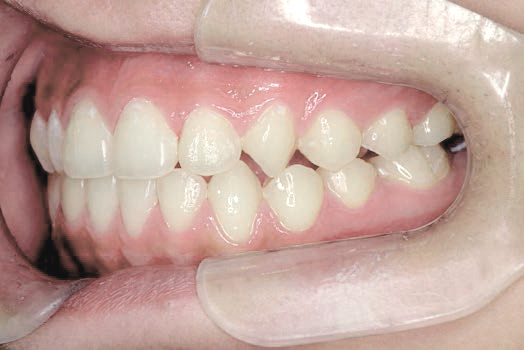

Aさん (矯正開始時:8歳)

Before

After

鼻がつまりやすく、口呼吸をしているために上あごが狭い状態でした。また上の前歯がかなり前へ傾いているため、お口をきちんと閉じていることができません。さらに、下の前歯もでこぼこしていました。

治療を終えて

装置によって上あごを拡大し、下あごを少し前へ成長させたことで、永久歯がきれいに並ぶスペースを確保しました。また、お口の機能が向上したことから鼻がよく通るようになり、口呼吸も改善され口も閉じやすくなったので顔の表情もよくなりました。

主訴・治療内容 下あごが後ろに下がり、出っ歯のようになっていることを心配して、無料相談に来院されました。

治療期間 2年半

費用 462,000円(税込)